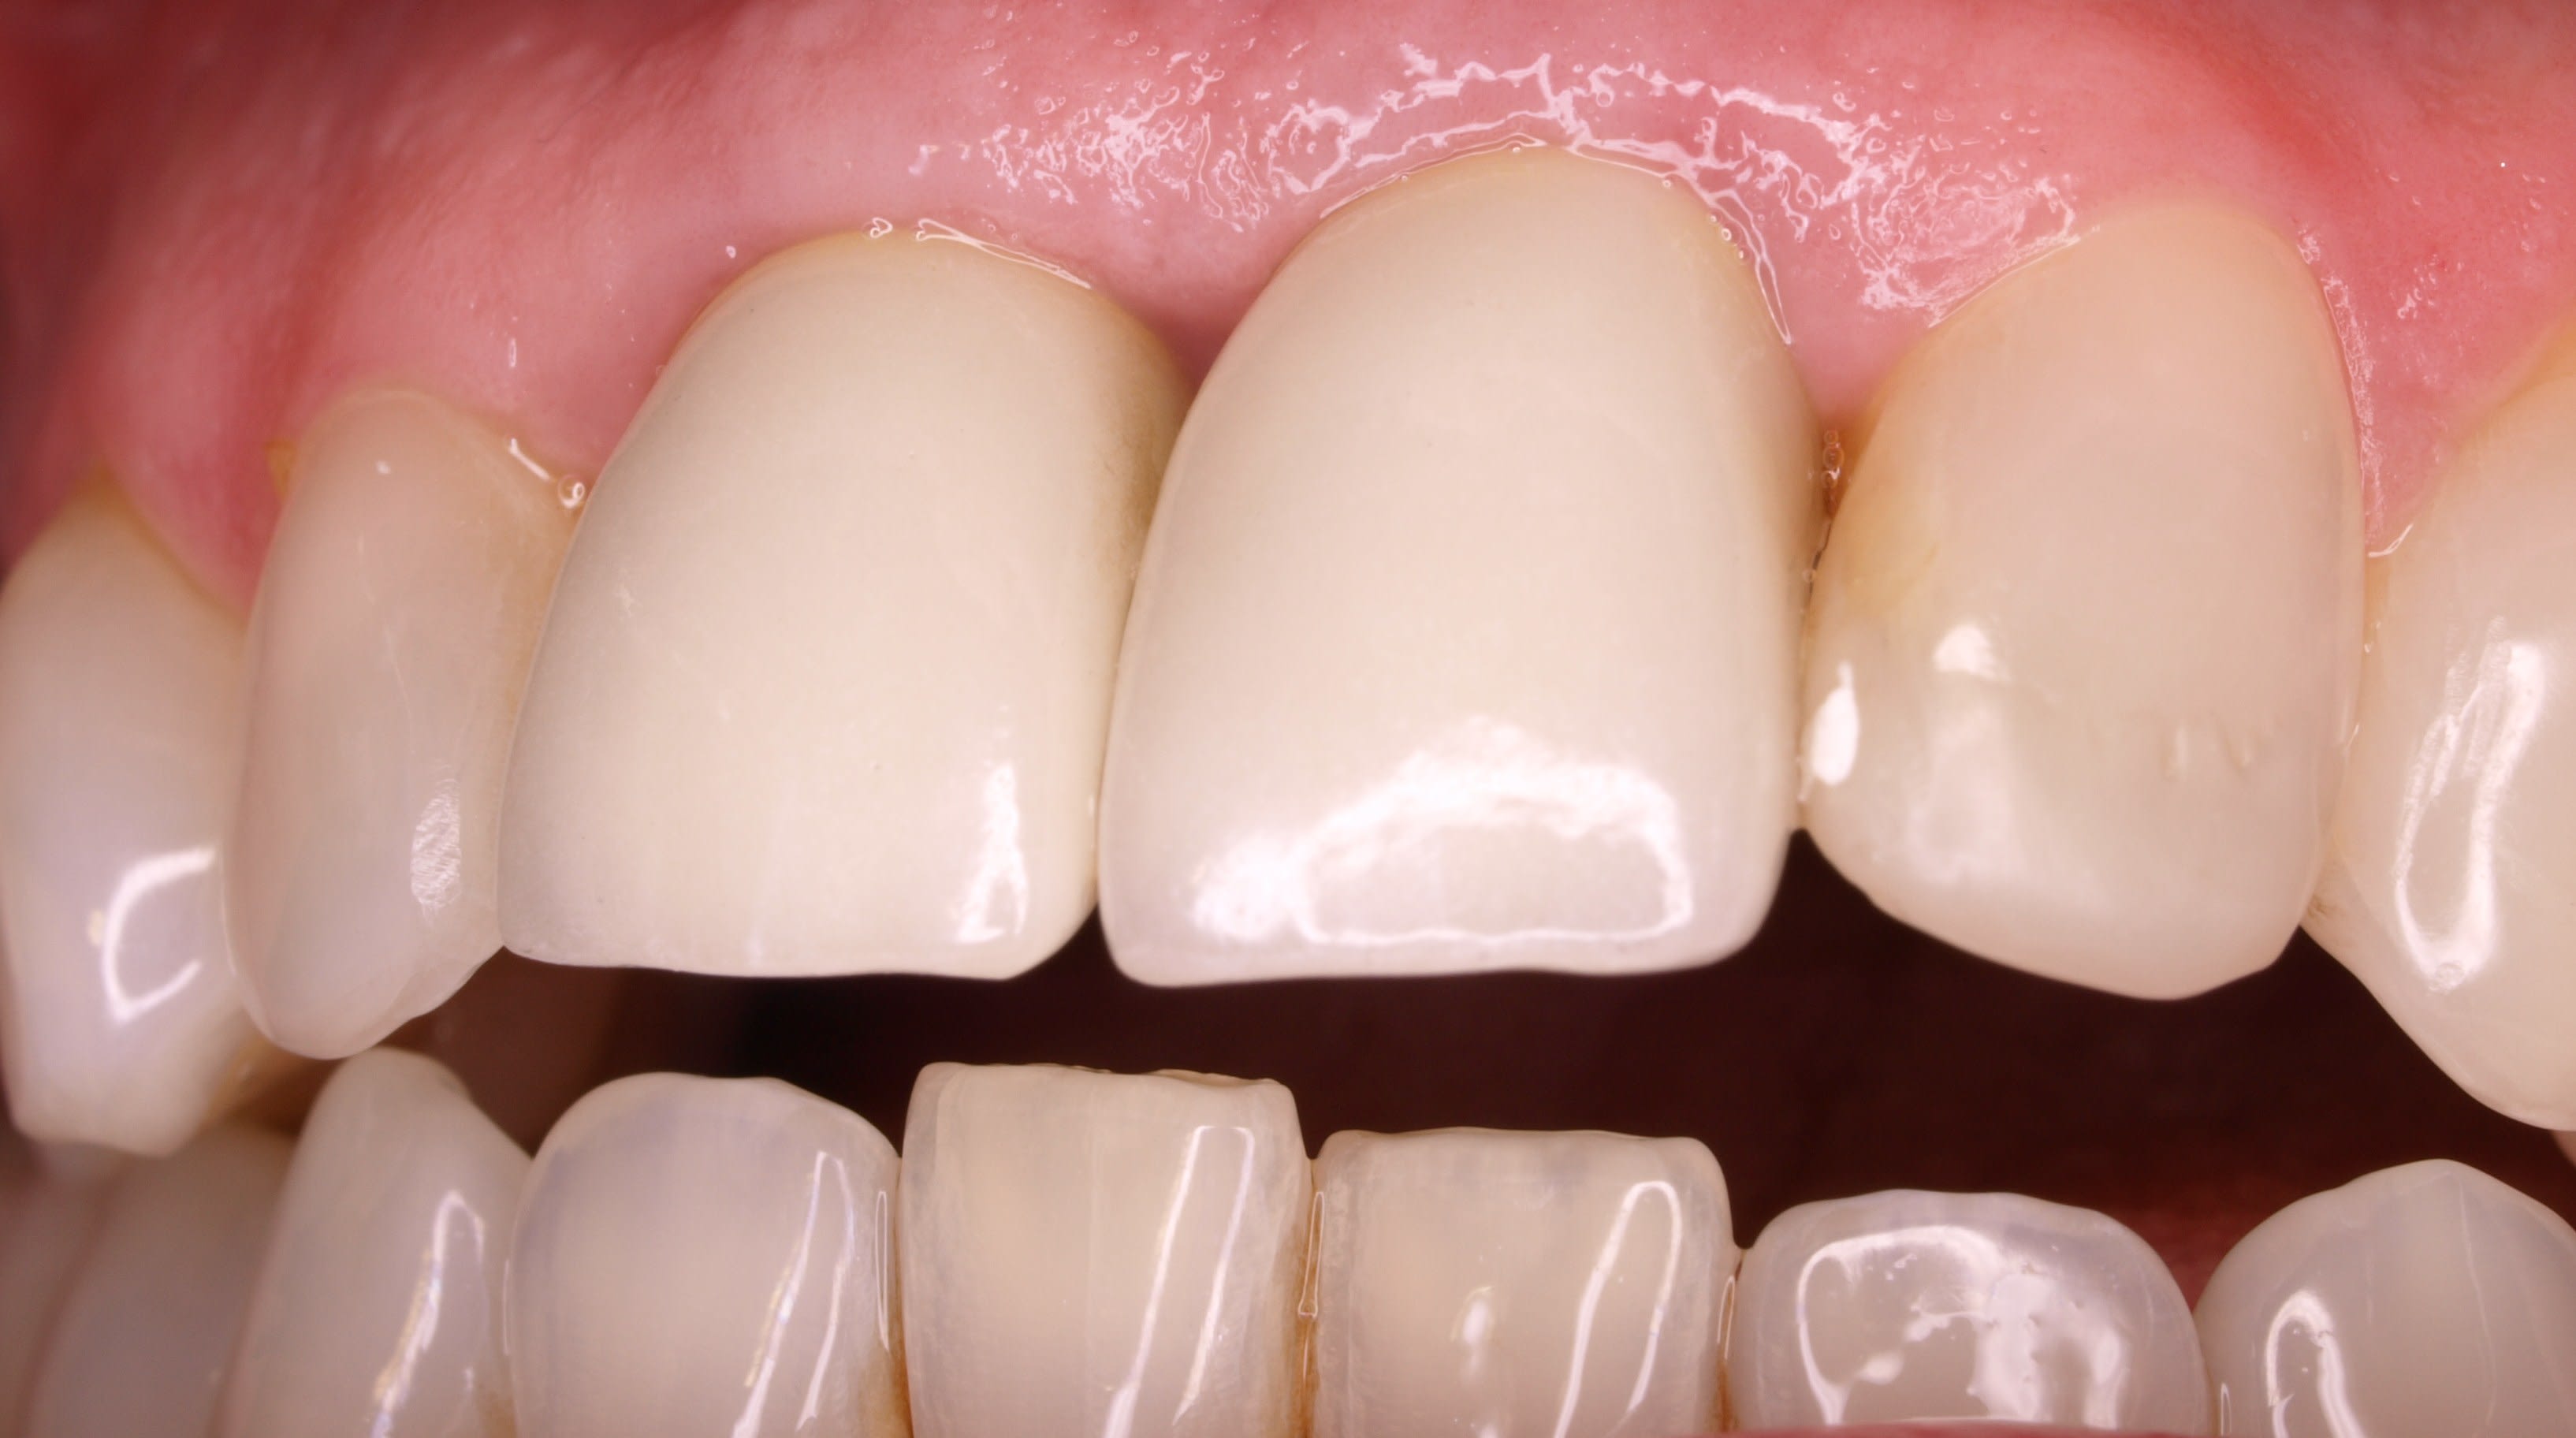

C'est une jeune femme qui a d'affreuses CCM faites il y a 8ans en surcontour gingival au niveau 12-11-21-22..

Ces CCM sont très volumineuses, débordant dans le sulcus avec une limite de préparation en congé hyperagressive et très sous gingivale... La patiente a un sourire gingival et on ne voit que cette gencive rouge violacée hypertrophiée..

le meme genre de cas avant et apres le jour de la pose

plus tard la papille s'est recrée .